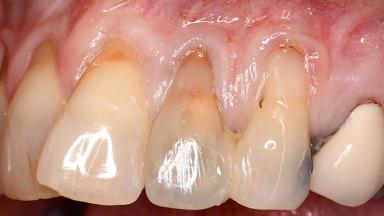

Early Implant Placement, Contour Augmentation, and Autologous Connective-Tissue Graft Using a Tunneling Technique to Replace an Upper Incisor with Generalized Gingival Recession

Variations in soft-tissue volume, evidenced either by an overabundance (Evian and coworkers 1993; Levine and McGuire1997; Dolt and Robbins 1997) or by a deficiency of soft or hard tissue can complicate implant-supported rehabilitations in the esthetic zone (Lorenzana 2008; Lorenzana and coworkers 2009). The present case illustrates the replacement of a failing upper left lateral incisor complicated by generalized severe gingival recession in the esthetic zone.